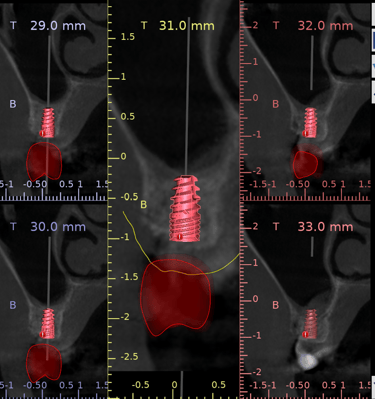

2.Simulación y evaluación: Se planifica digitalmente el implante para evaluar cualquier riesgo.

3.A partir del diseño digital, se obtiene una guía quirúrgica para las colocación precisa del implante.